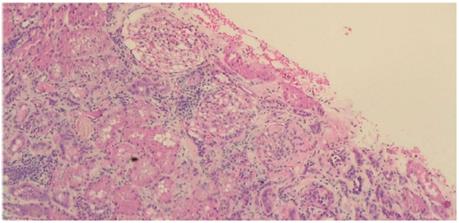

A 22-year-old male patient who had no pathologic antecedents in his medical record presented fever, olfactory amnesia, dysgeusia, diarrhea and anasarca at the time of admission to our healthcare center. After performing a PCR for SARS-CoV-2, the result came back positive. Among the laboratory studies carried out, elevated serum lactate dehydrogenase values (LDH, 274 U/L), hypercholesterolemia (261 mg/dl) and hypoalbuminemia (2.6 g/dl) can be highlighted. By contrast, creatinine test(1 mg/day) and uremia (38 mg/day) levels were normal. Additionally, the virus test panel for human immunodeficiency virus (HIV), hepatitis B (HBV), hepatitis C (HCV), cytomegalovirus (CMV) and Epstein-Barr virus (EBV) was negative. The tests for the immunological markers pANCA, cANCA, ANAS and anti-DNA were negative, and complement component levels were normal: C3 116 mg/dl (88-165 mg/dl) and C4 16.4 mg/dl (14-44 mg/dl). PLA2R antibody was not measured since it was not available. However, severe proteinuria was present (26 g/day). Urotomography revealed normal kidneys and pleural effusion. A diagnosis of pneumonia caused by SARS-CoV-2 and nephrotic syndrome was made. Treatment with furosemide (40 mg/day), enalapril (10 mg/day), spironolactone (25 mg/day) and atorvastatin (10 mg/day) was initiated, and kidney biopsy was performed. Light microscopy revealed eight glomeruli showing glomerulomegaly without any evidence of fibrous or cellular crescents. A pattern of minimal changes in the absence of any remarkable glomerular abnormality was identified, except for one observed glomerulus that presented segmental mesangial proliferation. Furthermore, no abnormalities in the basement membranes, duplication, spicules or double contour were identified. Alterations in the tubules, vessels, and interstice were not observed. Direct immunofluorescence studies revealed no immunoglobulin or complement deposits (Figures 1 and 2). From the ultrastructural point of view, it was possible to demonstrate changes associated with podocyte foot fusion in >80 % of the basal membrane extension, which constituted a diffuse podocytopathy (Figure 3). Two weeks later, the patient showed spontaneously significant proteinuria (0.5 g/dia), edema reduction, as well as negative PCR result for SARS-CoV-2 in a new exam, thus he was discharged.

Note: Light microscopy with Periodic acid-Schiff (PAS) stain showing normal basal membranes and mild mesangial hypercellularity

Source: the authors.

Figure 2 Case 1 - Light Microscopy (glomerulus image)